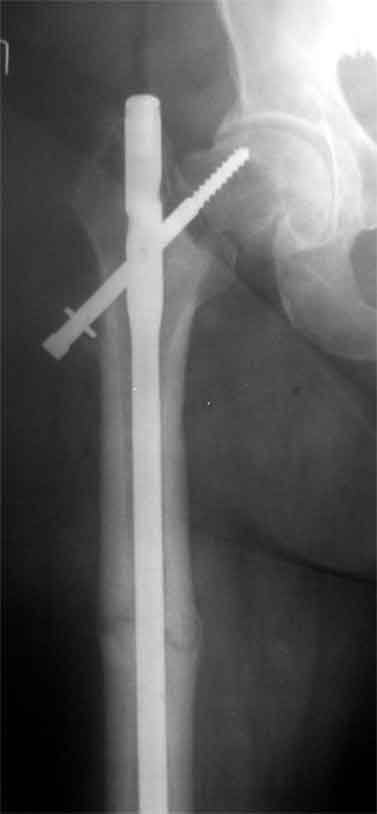

Доброго время суток, коллеги. Обратилась на консультацию пациентка 52 лет. травма и первичный остеосинтез перелома бедра около года назад, далее был обнаружен перелом шейки бедра (возможно ятрогенный), реостеосинтез реконструкционным гвоздем 8 месяцев назад. Конченость не опорна. В больнице, где выполнялись эти вмешательства предложили выполнить THR с длинной ножкой. Возможно ли в такой ситуации добиться сращения шейки при помощи каких-либо остеотомий?

Коллкега на представленных снимках имеется ротационная стабильность и плохо репонированный перелом. В данный момент думать об эндопротезтровании или межвертельной остеотомий рано, так как перелом диафиза бера еще полностью не сросся, я думаю, надо на данном этапе попытаться стабилизировать перелом шейки бедра конюлированными винтами, удалить проксимальный винт, попытатся сделать репозицию, хотя маловероятно, что получется добиться улучшения, и стабилизировать 3 конюлированными винтами и дать компресию, таким образом дать шанс, может перелом срастется до удаления штифта. Удачи

Применение одного импланта для лечения ипсилатеральных переломов резко ограничено из-за риска осложнениий, связанных с применением неадекватной фиксации. По литературным данным, осложнения после применения зарекламированных реконструктивных гвоздей для лечения ипсилатеральных переломов доходили до 56%.

Несостоятельность фиксации шейки не давала возможности срастись перелому, потому что запланированнная динамическая нагрузка в большинстве случаев прекращалалась из-за вторичного варусного смещения шейки.

Сегодня применяемые новые реконструктивные гвозди Intertan и Gamma 3, которые имеют возможности создания угловую стабильность за счет блокировки гвоздя и шурупа в проксимальном отделе бедра, пока

недостаточно изучены для восстановительных операции на шейке.

В идеале свежие ипсилатеральные переломы надо лечит отдельно каждый:

шейку паралельними шурупами, бедро ретроградным методом. При латеральных переломах шейки 130 градусный DHS с ретроградным гвоздем.

Тогда импланты, не мешая друг другу, создадут компрессию на бедре и скольжение в шейке.

В данном случае навряд ли можно ожидать образования сращения на бедре и еще имеется укорочение засчет варуса.

Для предоперационной планировки необходимо сравнительные ренгенограммы с другой стороны, которая точно укажет истинную длину конечности. КТ

поможет установит сращение на шейке и бедре. Восстановление длины можно сделать за счет вальгусной остеотомии оригинальным методом Blade Plate. На бедро шт ифт ретроградно или пластина, кому что нравится. На мой взгляд, еще имеется шанс спасти головку остеотомией.